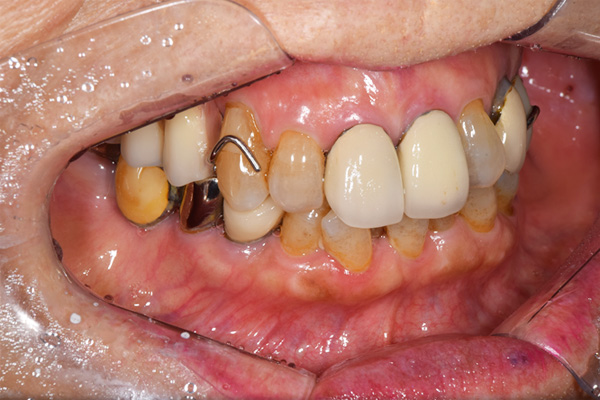

ケース1(自費の部分入れ歯)

前歯が折れて当院にいらっしゃいました。 過去に下の入れ歯を作ったが、合わなくなってずっと入れ歯をいれていらっしゃらない患者様でした。 これは奥歯で噛むことができないため、前歯で噛むことを繰り返したために、負担に耐えられなくなった前歯が折れてかぶせ物ごと 外れてしまったのだと考えられます。 痛くない、違和感の少ない、下の入れ歯を作ることがこの方のゴールであると考えられました。

金属を使用して、薄く違和感が少ない入れ歯が完成しました。 また、見た目にも気を使い、バネが見えにくい様な構造にしました。

入れ歯をお口の中にいれた状態です。前歯もMTMといって、歯を少し引っ張り出す処置を行なったことで、しっかり残せて、またかぶせ物をしました。

年齢 70歳・女性

主訴 前歯が取れた

治療期間 8ヶ月

治療費 .MTM:110,000円

.ファイバーコア:16,500円

.E-maxクラウン:110,000円

.義歯:660,000円

治療方針 長年使ってきた義歯の人工歯が磨耗し、臼歯部での咬合がすくなくなり、前歯部での接触が強くなったことで生じた前歯の破折なので、義歯も作り変える必要がある。

治療内容 前歯部MTMと同時に審美面の回復。

MTM中に義歯の作成も同時に行う。

最終的に義歯と前歯のクラウンを同時にいれる。

義歯は下顎で、しっかり噛めること、違和感の少ないものという希望があったため、なるべく入れ歯を薄く作成するために金属をしようした義歯とした。

また、見た目もあまり義歯が目立たない様に、バネの部分を見えにくいように作成した。

特記事項 歯にもともと入っていた金属の種類によっては、歯自体の変色を治療で変えられないこともある。 義歯は作ってから痛みがでることがありますが、それは調整を行うことで痛くなくすることができます。